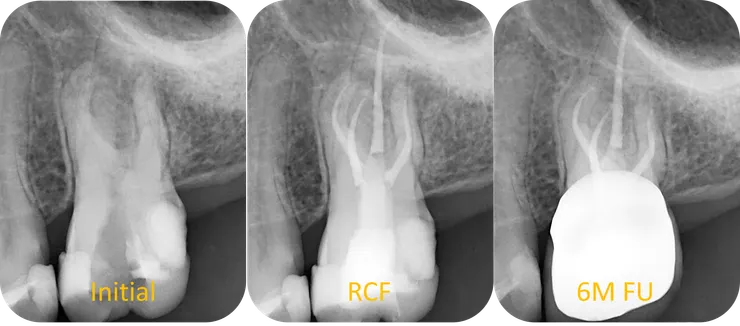

從 initial v.s. RCF 可以看得出來,因為 DB & MB2 canal 過彎不易,犧牲了不少 pericervical dentin. DB orifice 上方也是類似的情況,有一區蓋過來的 dentin. 但因為 DB 洞明顯的比 MB2 洞大多了,所以我沒多加處理。就這樣試著把 file 督進去......

但還好因為 heat treated NiTi file (PTG F1) 過彎能力佳,以及過程中且戰且走地以正確的順序使用正確的工具,而因此不需要把第一個彎以上全部拉直,得以保留足夠的 pericervical dentin.

這 case 因為發生了一些小插曲,搞了七個 appointment 才 RCF.

然後就在第三個 appointment 順利 RCF.DB orifice 上方也是類似的情況,有一區蓋過來的 dentin. 但因為 DB 洞明顯的比 MB2 洞大多了,所以我沒多加處理。就這樣試著把 file 督進去......